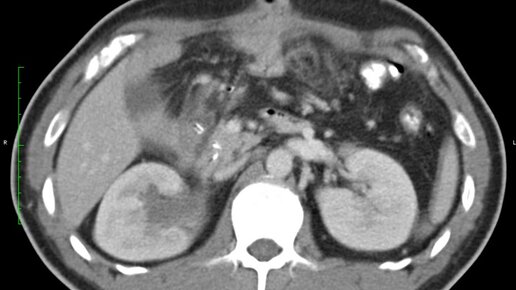

Что видно на КТ забрюшинного пространства (видео)